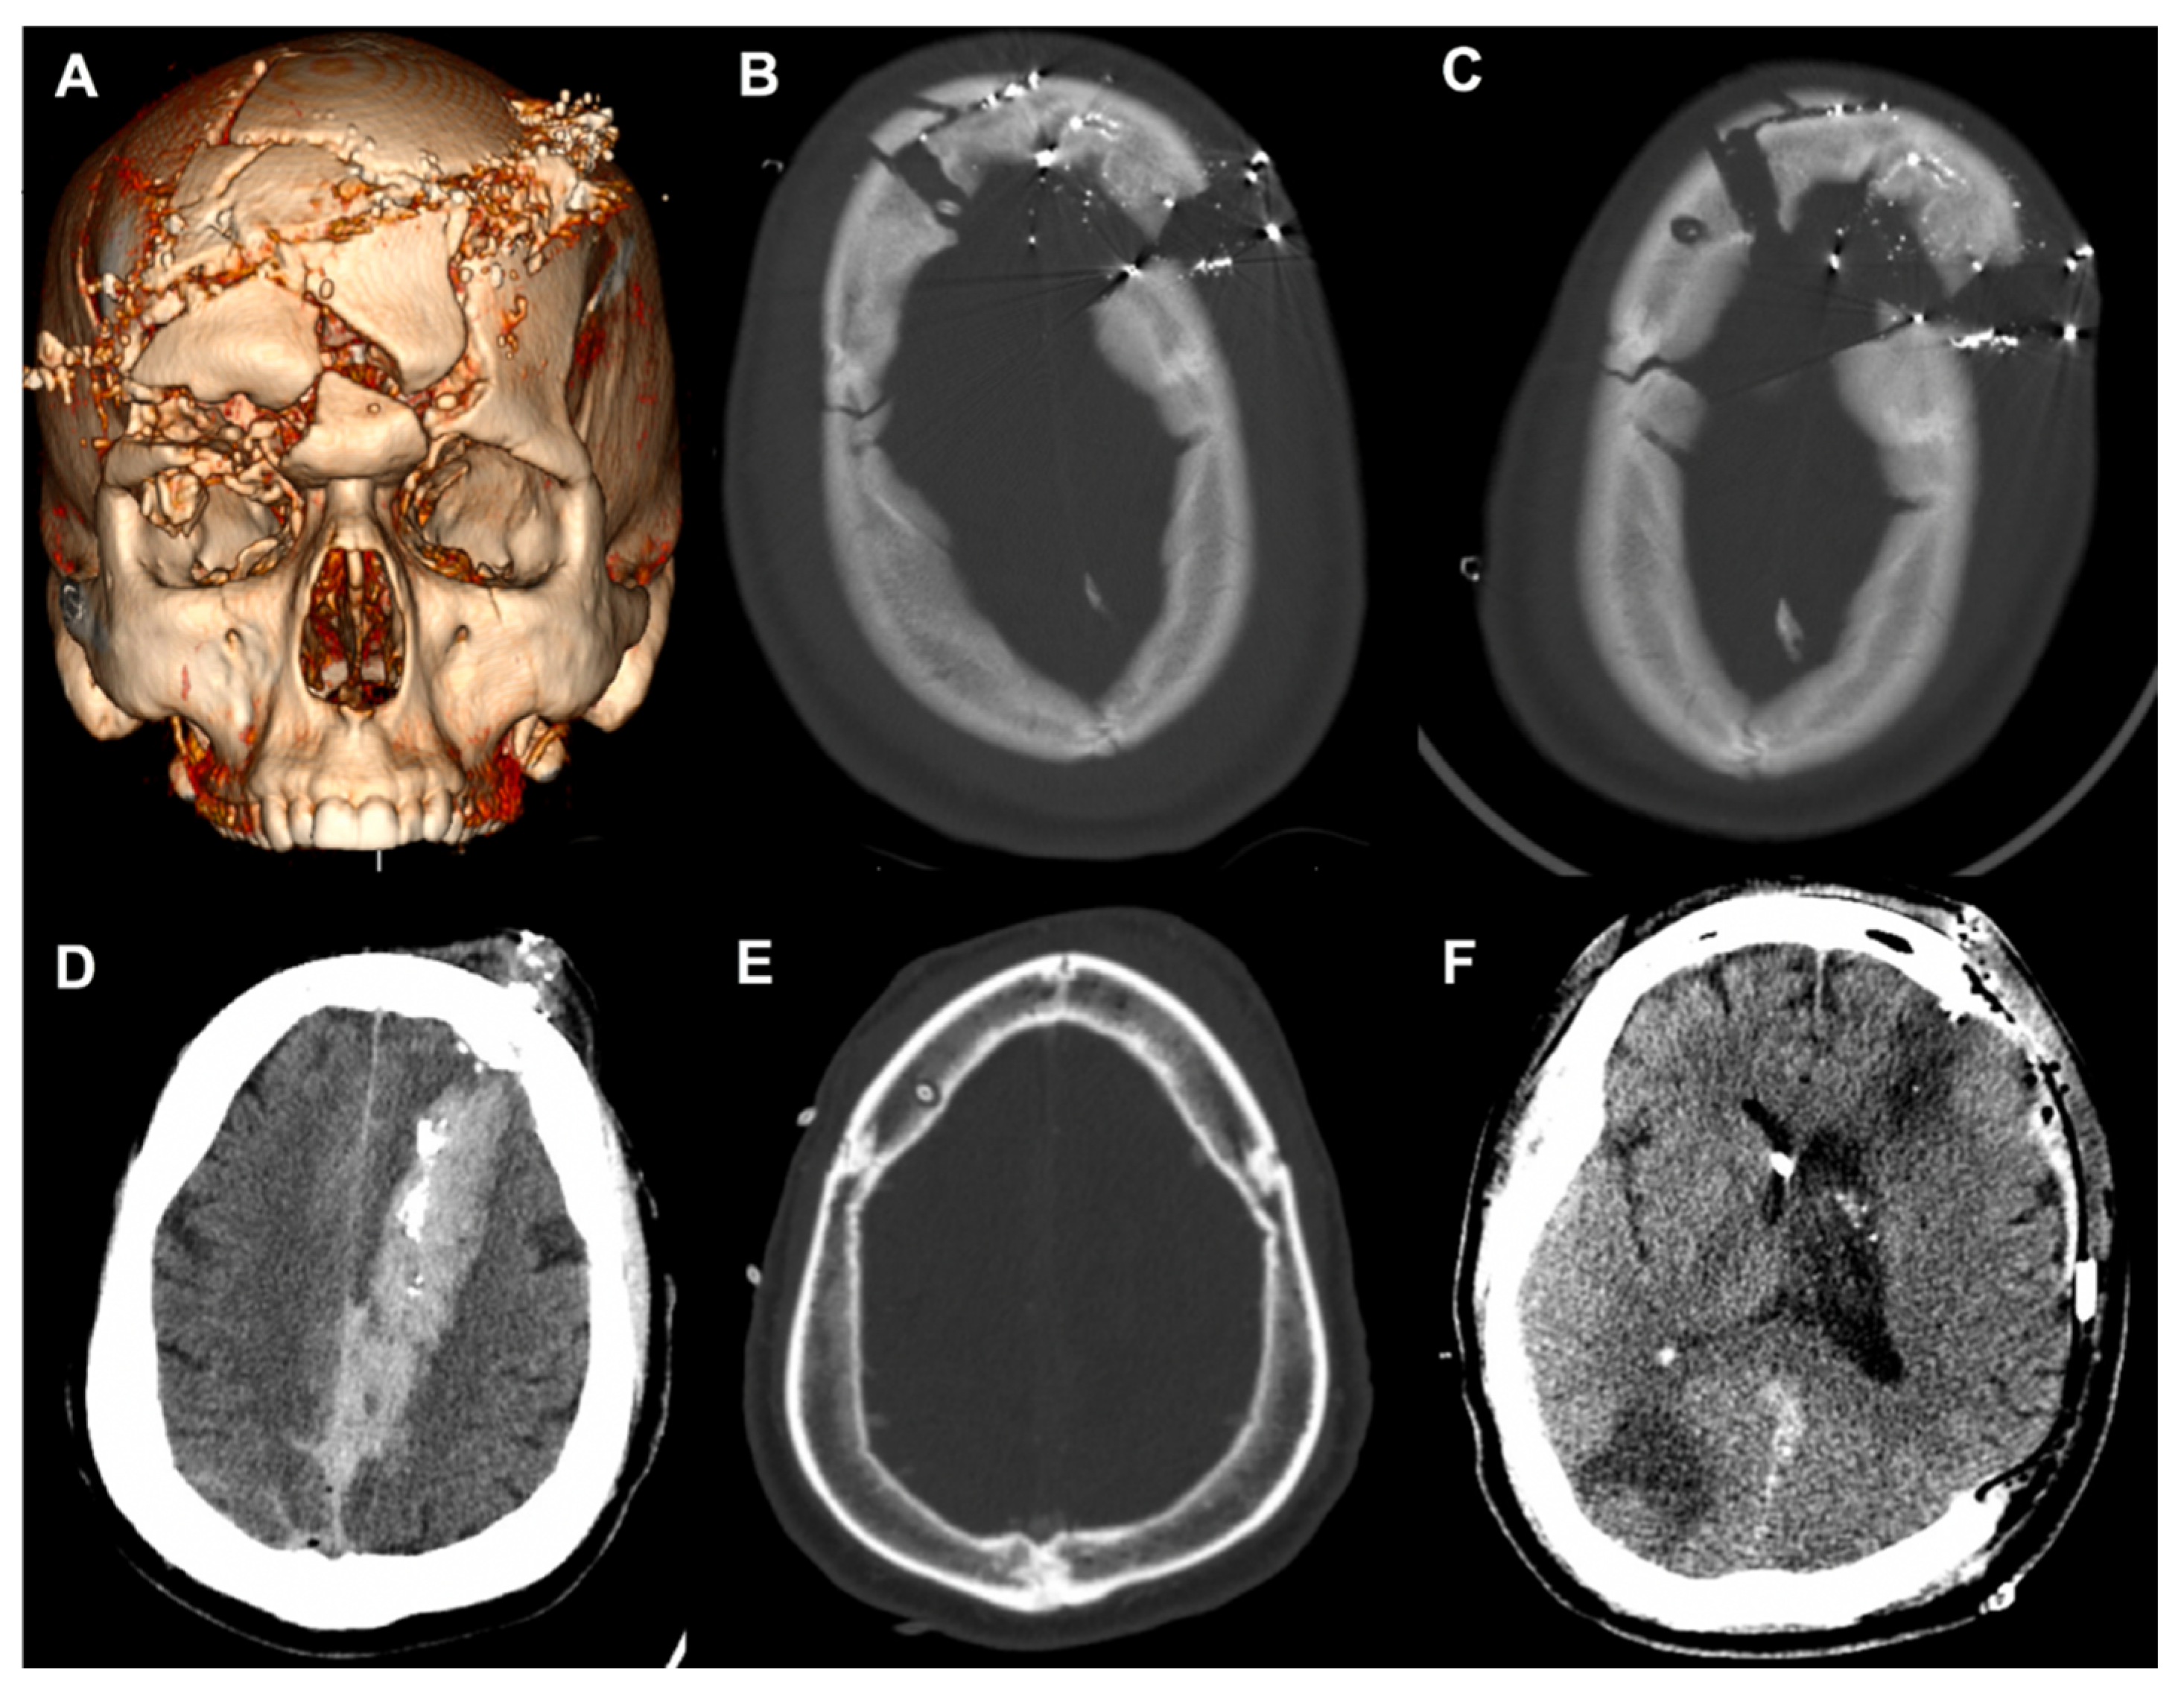

A 23-year-old male with self-inflicted gunshot wounds (GSWs) to the head with a 0.357 caliber bullet was brought in by EMS with open cranial wounds and orbits head-wrapped. CT imaging showing the multicompartmental intracranial bleed, as well as the severe craniofacial fractures, are depicted in Figure 5A. These injuries included comminuted bilateral frontal calvarial fractures that involved the frontal sinuses and anterior skull base and bone fragments in the bilateral orbits, with a right open-globe injury. The initial GCS score was 7T, and the patient was intubated for respiratory distress. In accordance with the current guidelines on the management of a penetrating TBI, a right-sided EVD was planned at the Kocher’s point [12].

Figure 5.

Case presentations of complex craniofacial trauma. (A) Three-dimensional reconstruction of Case 1. (B) Initial placement of the right frontal EVD through splayed fractures. (C) Power drill craniostomy next to the fracture to replace the initial EVD. (D) Case 2 demonstrating a penetrating injury with a left frontal entry wound extending into the occipital lobe. (E) Right frontal EVD placement using the power drill. (F) Axial CT after left-sided decompressive craniectomy. EVD, external ventricular drain; CT, computed tomography.

Initially, when using the manual twist drill, the neurosurgeon worsened the depressions of the comminuted fractures with any exertion of downward force to initialize the drilling. The EVD was directly threaded through the splaying of the frontal fractures (Figure 5B), but soon after, the ventricular catheter kinked off at the edge of the cortical table and required replacement. The Phasor power drill was used to create the burr hole 1 cm posterior and lateral from the fracture line (Figure 5C). The EVD was in place for 14 days without malfunctioning. Similarly, a 54-year-old male was found after a self-inflicted GSW with a left frontal entry wound extending through the left occipital lobe (Figure 5D). The initial GCS was 10 T, and with concern for elevated ICP and neurologic worsening from cerebral edema, an EVD was accurately placed (Figure 5E) and assisted with ICP management for 10 days. The patient required a left-sided DHC due to progressive edema and midline shift.

Case 1 highlighted a range of clinical and radiographic factors that the neurosurgeon had to process and to make adjustments. Polytrauma is typically defined as an ISS of 16 or higher, which made up a majority of the patients in the present study. It is known that moderate and severe TBI patients with polytrauma complexes have poorer functional outcomes [14,15,16], and patients with maxillofacial trauma commonly have orbital or nasal fractures along with TBIs [17]. Patients with penetrating TBIs from GSWs are a subpopulation with high rates of complex craniofacial trauma, and this class of patients carries high morbidity and mortality [18,19]. For Case 1, initially with the manual twist drill, the operator created worsening depressions of the comminuted fractures due to any exertion of downward force that would be necessary to initialize drilling. The grip form of the power drill converts drilling into a single-handed procedure [20], freeing the non-dominant hand of the operator to provide further stabilization on the drill stop extension. Additionally, the rotational force from the power drill allows for easier engagement with the cortical skull and reduces the translational force.

The TBI patient population is susceptible to coagulopathy, although its pathogenesis remains poorly understood [21,22]. Along with poor anatomic landmarks, this further propagates the iatrogenic risk of a blind bedside procedure without hemostatic agents. Similar to improvements in the release mechanism of contemporary perforators to reduce complications [23], the drill stop extension of the power drill is a simple guide that can sustain 50 lb of plunging force without causing depth-plunging of any clinical relevance. As Case 2 showed, TBI patients can have a small ventricular caliber and cerebral edema, which can make cannulating the ventricular system difficult [24]. In our patient, with increased concern for elevated ICP and neurologic worsening from cerebral edema, an EVD was accurately placed to assist with ICP management. The Ghajar Guide was introduced in 1985 to project the ventriculostomy in a perpendicular trajectory to the target of the foramen of Monro in patients with small or slit ventricles [25]. Similar in concept but for the burr hole, the drill stop hubs the skull surface to provide the advantage of preventing the drill tip from skiving and to facilitate perpendicular drilling.